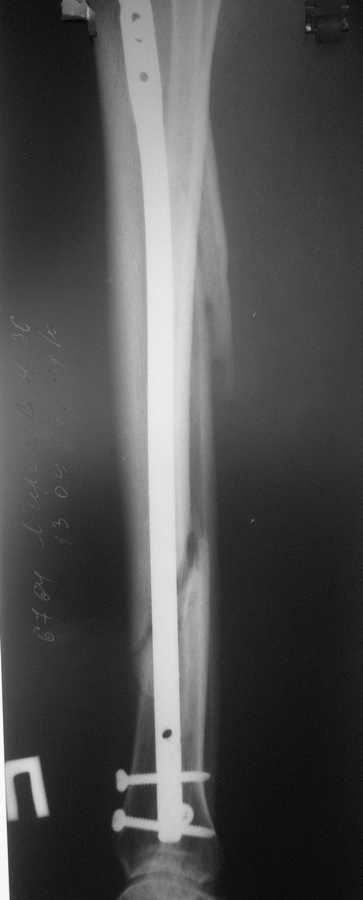

В январе 2009 года нами оперирована пациентка с переломом н\3 голени штифтом Expert. Динамизация через 4 месяца, пациентка при этом уже ходила с тростью. Дома периодически передвигалась без дополнительной опоры. В настоящее время - через 9 месяцев с момента операции периодически в вечернее время беспокоят ноющие боли в места перелома (не постоянно). При беседе выяснено, что боли чаще беспокоят после того, как днем она походит по дому без трости. Пальпаторно по гребню берцовой кости болей нет, но по задне-внутренней поверхности б\б кости пальпирутеся западение на уровне места перелома.В чем ошибка??? и что делать???

Недостаточная стабильность. Не использованы все возможности дистального запирания, нет самого проксимального из дистальных винтов. Два винта из трех коротковаты. В результате при диинамизации появился диастаз.

Тут есть уже опасность перелома стержня по ближайшему к перелому отверстию. Так что правильнее сделать реостеосинтез с рассверливанием. При введении гвоздя в дистальный отломок использовать отклоняющую спицу

или винт, чтобы стержень оказался не у переднего кортекса, как сейчас, а где и надо - посередине. Это обеспечит еще и встречно-боковую компрессию.

Да, динамизация поздновата. Да дистальный отломок заперт одним винтом, два другие короткие, еще дно отверстие пустое...

Этот 9-ти мм. стержень ExpertTN вряд ли скоро сломается, если, конечно же, пациентка не имеет большого веса (>100 kg). Перештифтовать более толстым штифтом с рассверливанием, пожалуй, самый надежный вариант, но не факт, что единственный. Вполне правомочно подумать просто о косой остеотомии малоберцоыой кости (зачем резекция???) в средней 1/3 и попытке дополнительной стабилизации дистального отломка путем запирания штифта через свободное отверстие (наиболее проксимальное из дистальных) и замены двух самых дистальных винтов, причем косой самый дистальный лучше провести в другой плоскости. Возможно этого будет вполне достаточно для сращения...а вот периодически возникающие боли могут и остаться(((

По снимку гвоздь сидит плотно в узкой части большеберцовой, а на периферии нестабильная блокировка. Динамизация работает в течение первых 8 недель.